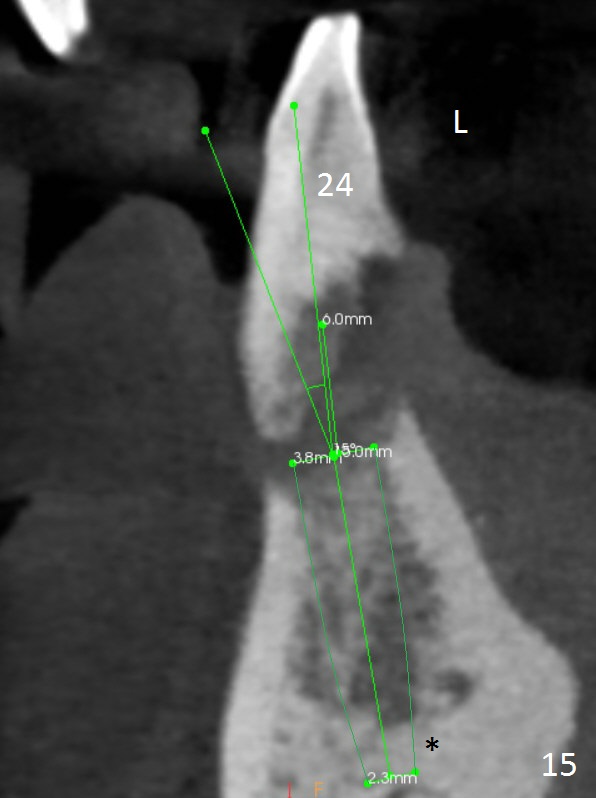

Class II Division II malocclusion (Fig.2,6) will make it difficult to restore #23-26 implant-supported FPD. Although the teeth #7-10 may need to be replaced later (Fig.7,8), enameloplasty will be conducted for #7-10 (Fig.9 white area; Fig.12 black circles (gross reduction)) prior to #23-26 extraction and implant placement (Fig.10). To be flexible in restoration (angulation) and possible future hybrid denture, 2-piece narrow implants will be placed (3.0 or 3.3 mm) instead of 1-piece ones. In fact CBCT shows that the narrowest regular implant (3.8 mm) can be placed in the lower anterior region (Fig.13-15).